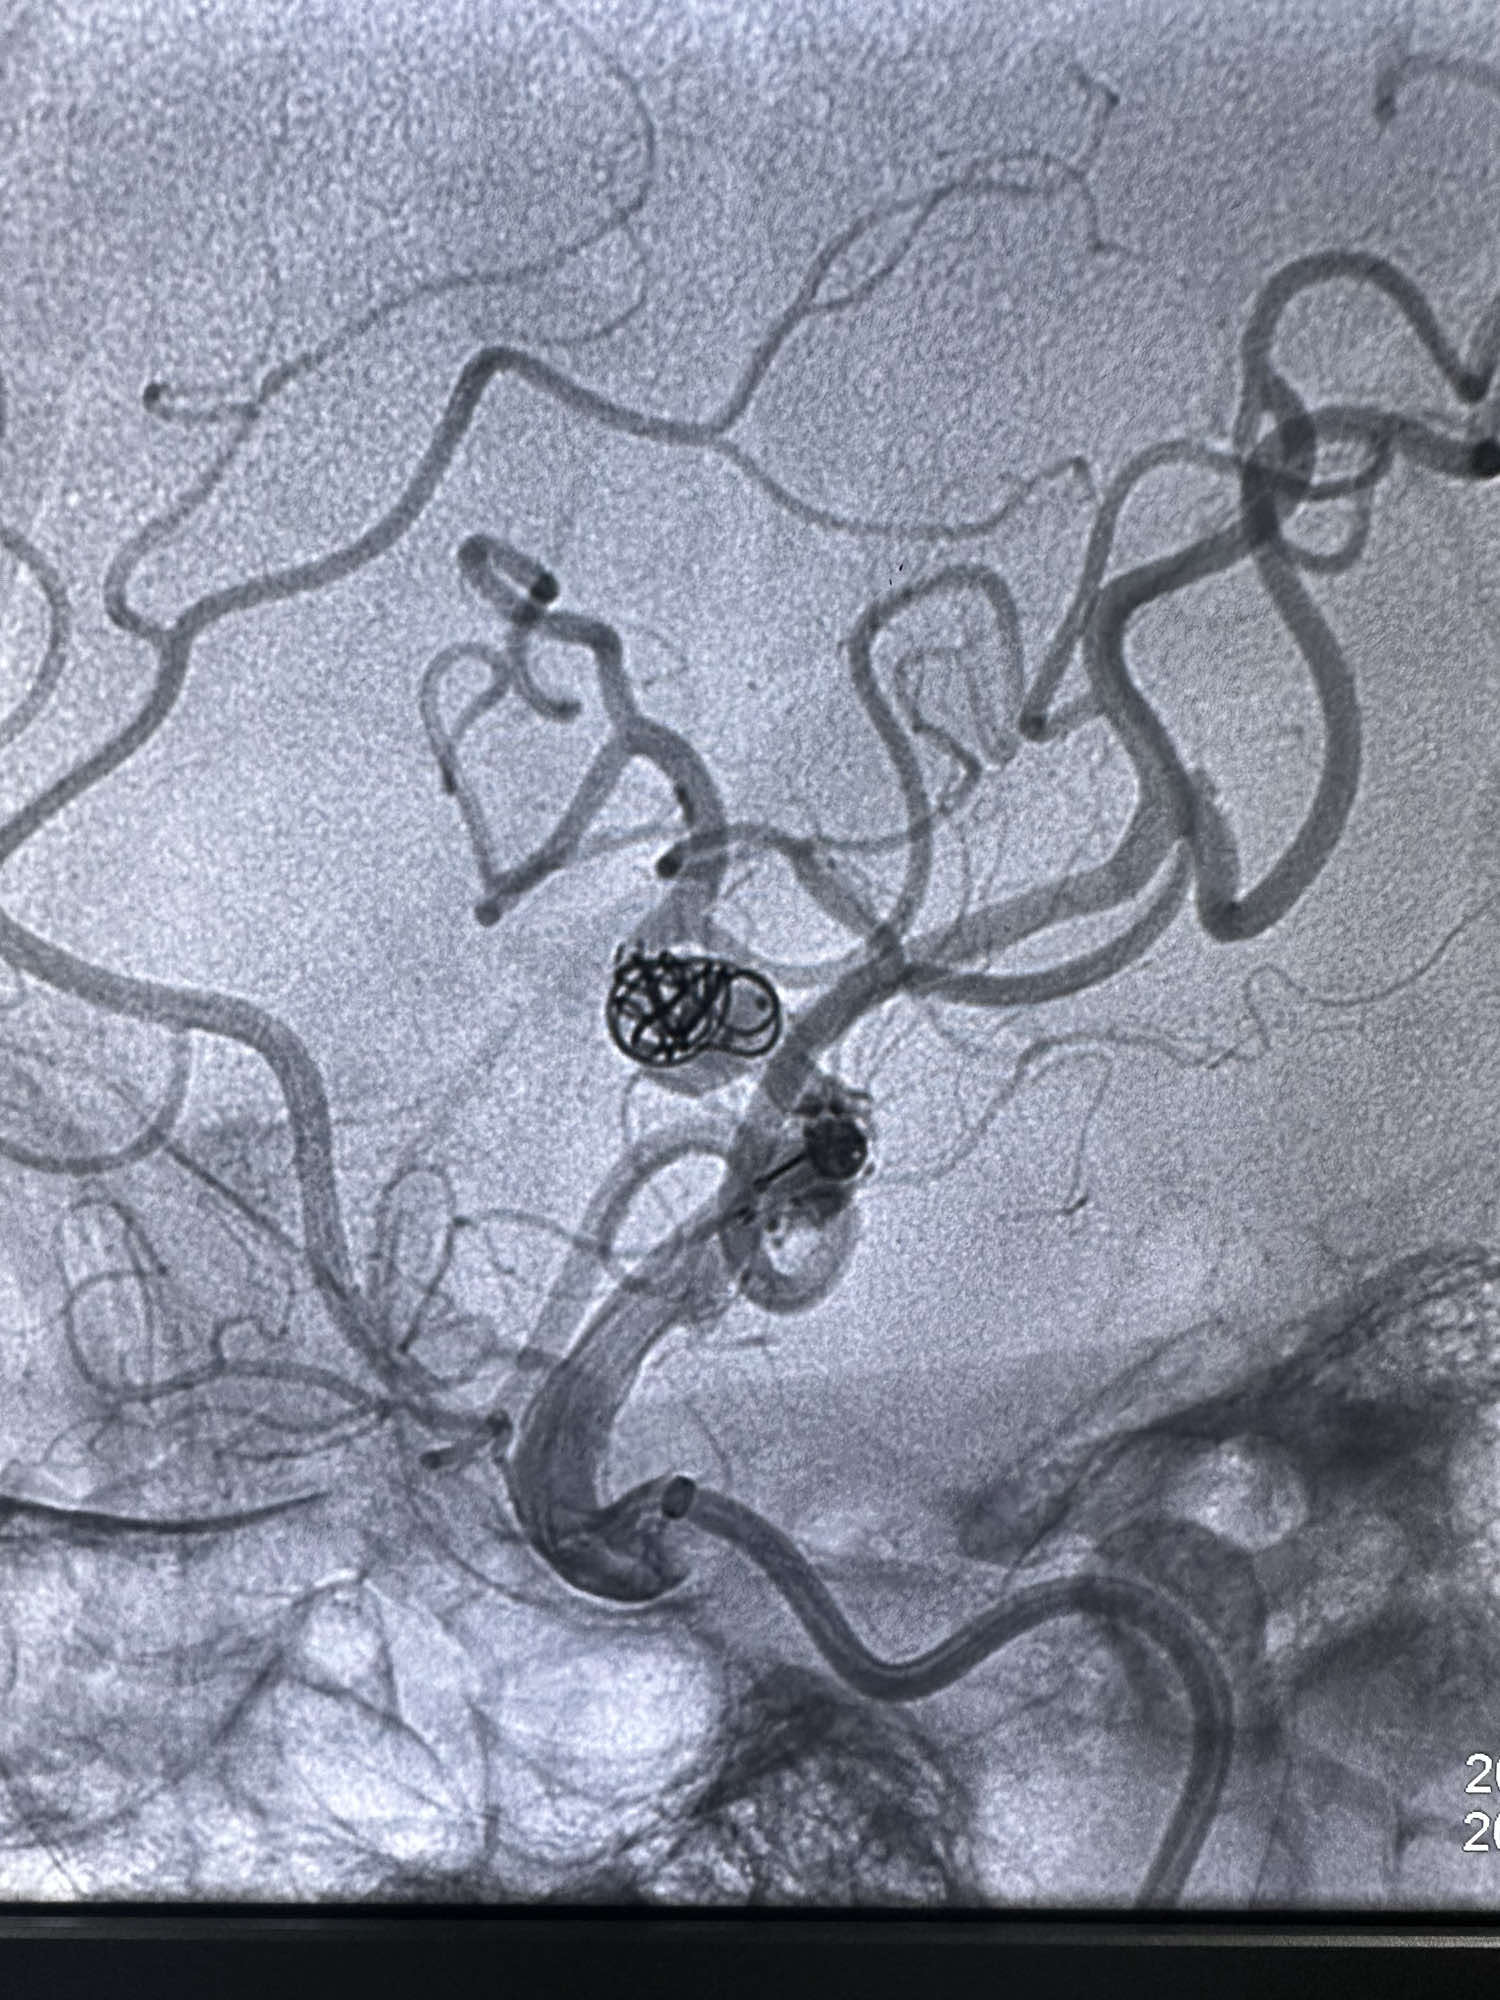

最后骨窗的形态

最后造影显示动脉瘤不显影

最后正位造影

侧位